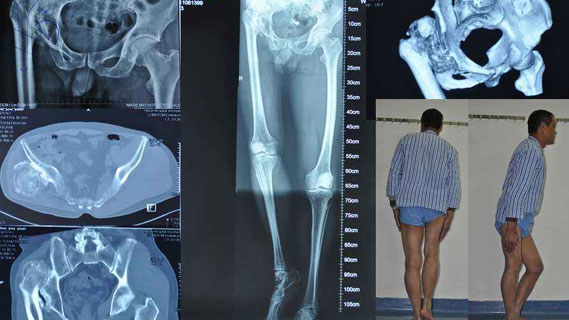

红会许鹏主任手术治疗发育性髋关节发育不良并髋关节骨性关节炎_西安市红会医院许鹏_寻医问药专家网

髋关节发育不良的保髋治疗